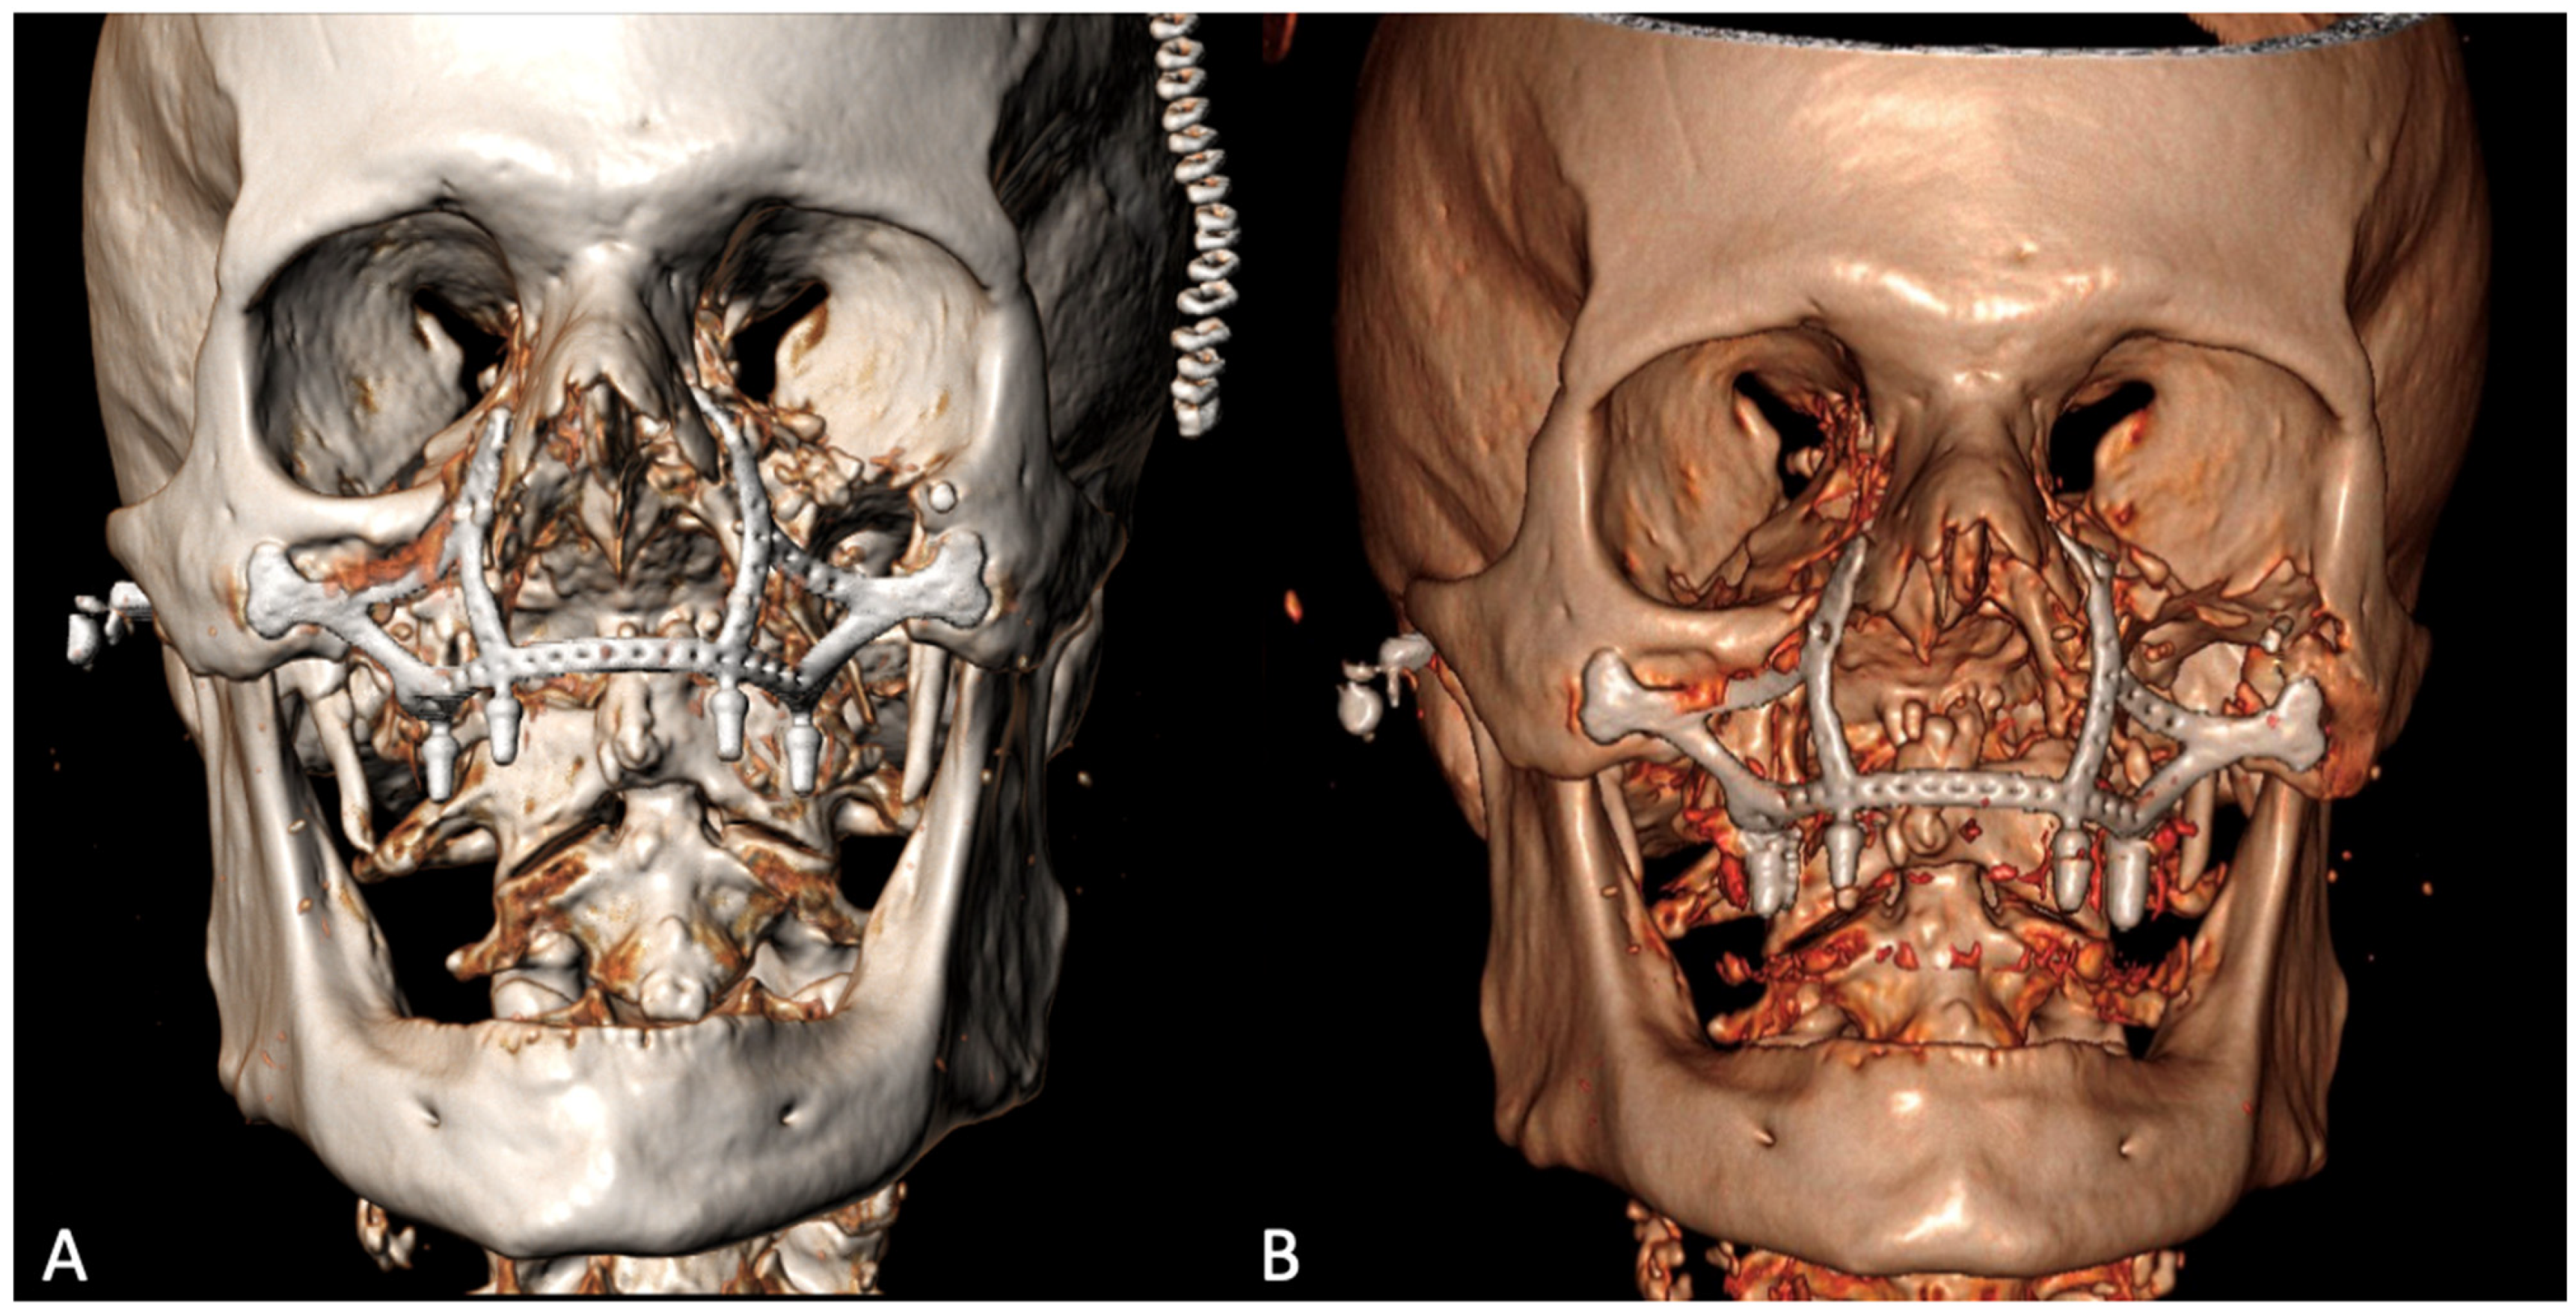

The histological examination confirmed the diagnosis of squamous cell carcinoma with bone infiltration and clear resection margins. The patient was a candidate for adjuvant radiotherapy, which, however, was not performed due to his advanced age and poor compliance. The post-operative 3D CT showed the correct positioning of the implant, adhering to the virtual planning, and its stability over time [Figure 6].

Figure 6.

Post-operative 3D CT scan 9 days (A) and 6 months (B) after the surgery.